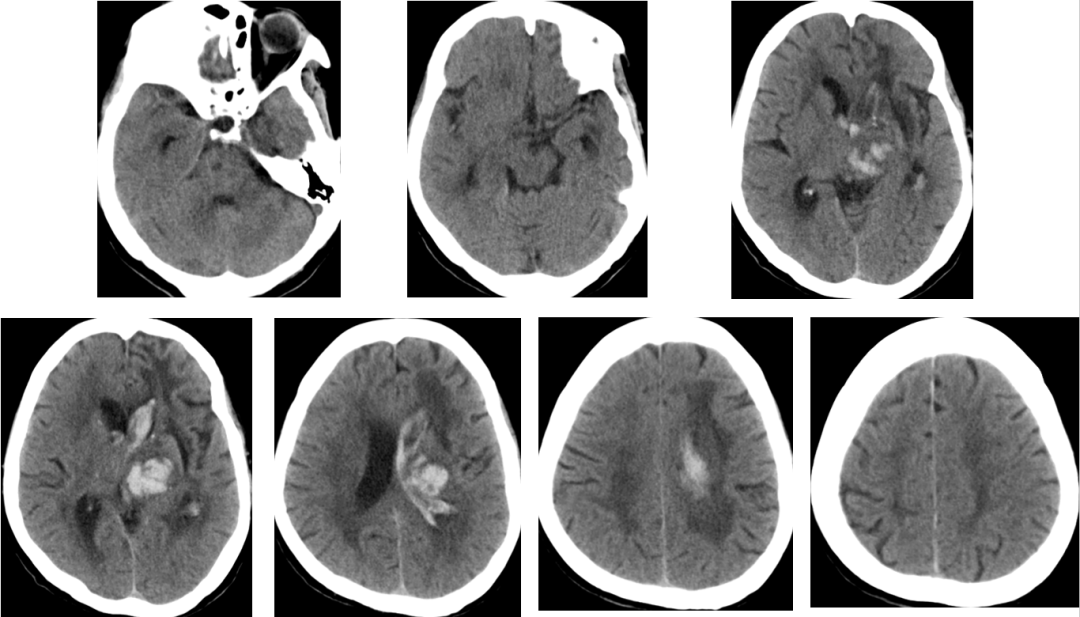

2014-12-2 CT

患者生命征平稳,精神可,一般情况好。

神经系统检查:神清清醒,有遵嘱动作,反应稍迟钝,左侧瞳孔2.5mm,右侧瞳孔3mmm,对光反射均稍迟钝,右上肢肌力粗测约2级,右下肢肌力粗测约3级,肌张力正常,左侧肢体肌力及肌张力粗测正常,右侧巴氏征阳性,余神经系统查体不能配合。

转院康复治疗。